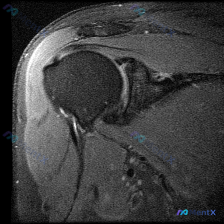

最近整理了一份肩部MRI的病例讨论材料,患者主要问题是肩部疼痛,但问题明确指向"盂唇病变"范畴。先看T2冠状位图像的关键发现: 1. 冈上肌腱在肱骨大结节止点处有显著高信号,连续性可能中断 2. 肩峰下-三角肌下滑囊有明显的高信号积液 3. 关节盂唇区域信号存在改变 大家觉得这个病例更符合哪种诊断?...

整理了一份有意思的肩关节MRI读片病例,问题一开始聚焦在「软组织积液」上,但梳理下来发现这个病例很容易踩坑,分享一下我的思路。 一、影像基本信息 这是一份肩关节冠状位T2序列MRI,我们按结构逐层看一下观察到的征象: 1. 冈上肌腱:肱骨大结节止点处可见条带状局灶异常高信号,贯穿肌腱全层,从关节面延...

最近看到这份肩部MRI病例,问题问的是影像里的软组织积液怎么解释,整理了完整的读片和分析思路分享给大家。 一、影像基本信息 这是一张肩关节冠状位T2序列MRI,扫描范围覆盖肩峰、肩锁关节、冈上肌肌腱、肱骨头、肩关节间隙和三角肌,我们先明确正常信号基准:T2序列正常肌腱是低信号(黑色),关节液、水肿是...

看到一个肩关节MRI影像分析的病例材料,影像为冠状位T2加权图像,主要发现如下: 1. 冈上肌腱远端附着处全层撕裂,T2序列显示高信号液体填充 2. 肩峰下-三角肌下滑囊内有明显积液 3. 盂肱关节腔内有显著液体潴留 用户的核心问题是关于「盂唇病变」的可能性。这个病例有几个点值得讨论: - 冈上肌腱...